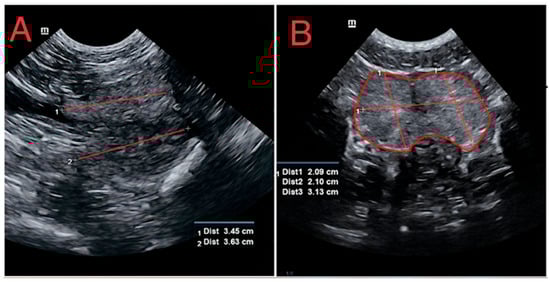

3.2. Ultrasonographic Evaluations of Prostate Glands

4.2. Ultrasonographic Evaluation